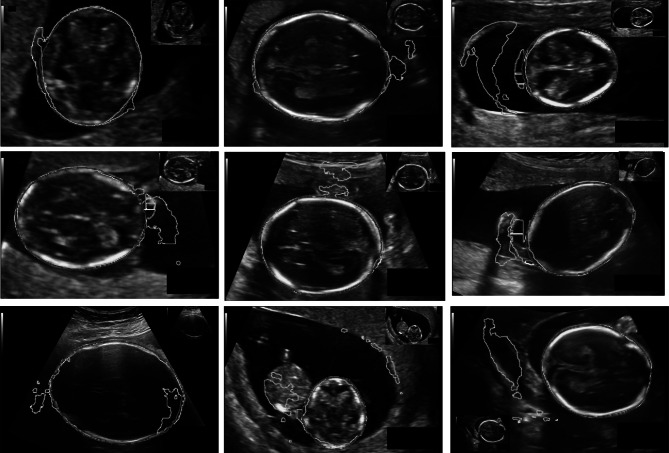

Figure 7 shows representative fetal head segmentation results by three deep learning models: U-Net, V-Net, and Attention V-Net, in order to demonstrate the effect of the attention module. The Attention V-Net model produced more accurate segmentation results than U-Net and V-Net and was the closest to the gold standard among the three models. Incorporating the attention mechanism can better capture the specific position of the fetal head, especially in the blurred head edge.

Fig. 7.

Fetal head segmentation results on validation sets by different deep learning models. a–c Fetal ultrasound image of the thalamus plane. d–f Segmentation by the U-Net model. g–i Segmentation by the V-Net model. j–l Segmentation by the attention-gated (Attention) V-Net model. m–o Manual segmentation as the gold standard. p–r Final fetal head contours (green: Attention V-Net; red: gold standard)